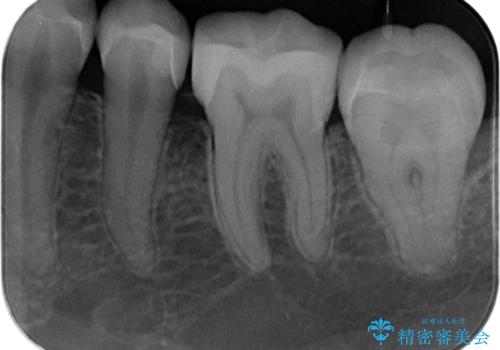

- メンテナンスの患者様です。歯間ブラシをすると染みるとの事で精査したところ歯と歯の間に虫歯が見られました。

拡大鏡下で虫歯を取り除きe-maxインレー治療を行いました。